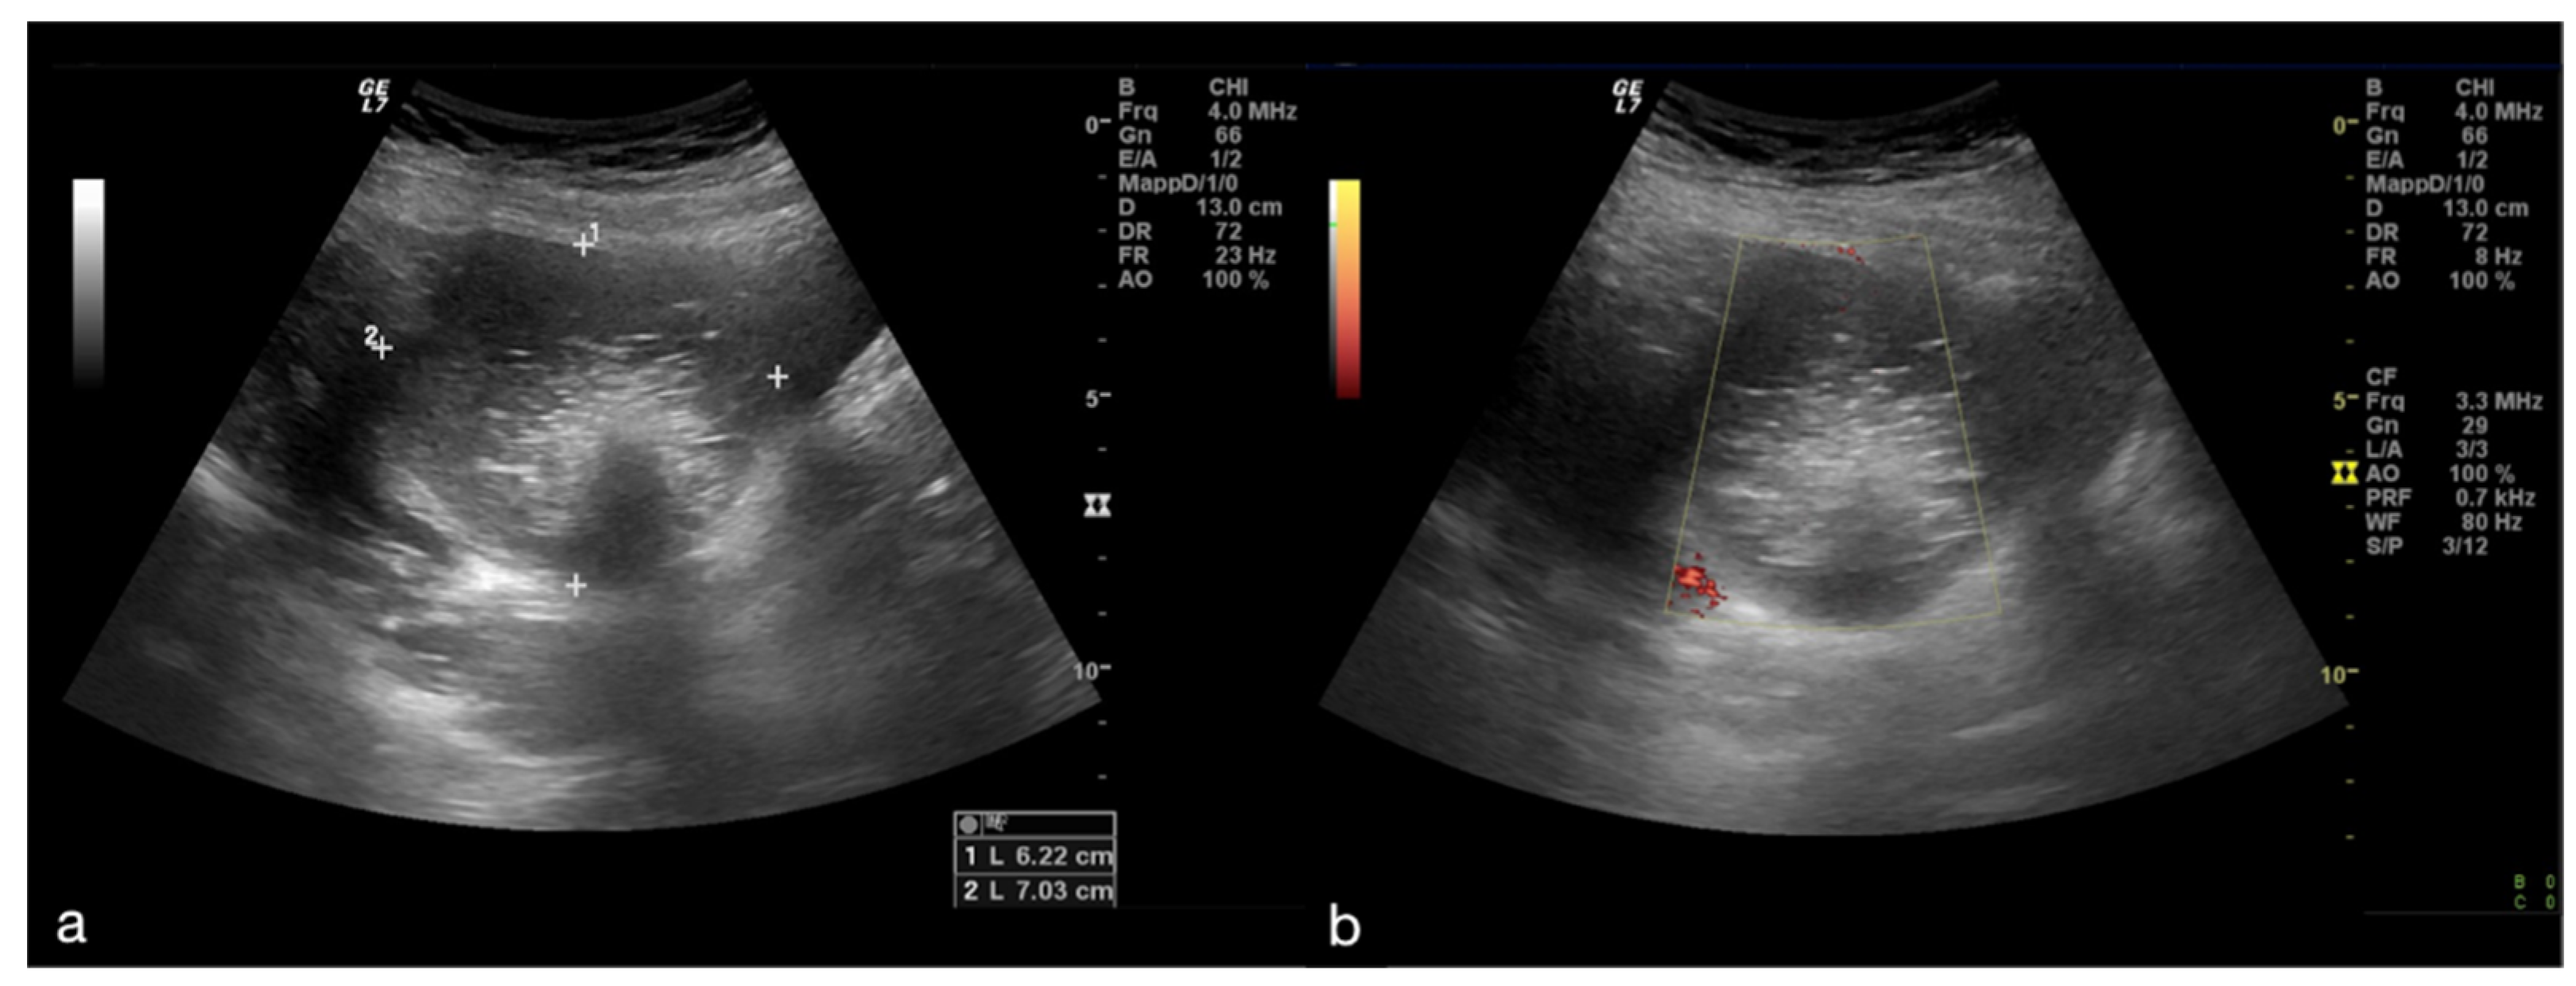

The ovary may be found in an abnormal position, close to the midline of the uterus, higher or lower in the pouch of Douglas, or displaced to the contralateral ovarian space [1,4,5]. The ovarian echotexture shows a hyperechoic central stroma due to the vascular congestion, associated with small peripheral follicles, with a “pearl necklace” appearance and, in the most advanced stages of vascular impairment, a diffusely uneven stroma due to the presence of focal haemorrhages and necrosis. The pathognomonic finding, however, remains the identification of the twisted vascular peduncle (“whirl” sign or “vascular vortex”), obtained by transversal scans along the central axis of the pedicle (Figure 2) [1,2,3,4,5].

The twisted and congested peduncle may appear as an indistinct adnexal mass adjacent to the twisted ovary. The colour Doppler examination allows for the assessment of the degree of torsion, the time elapsed from the beginning of the disease and therefore the degree of vascular compromise [1,2,3,4,5]. Vascular colour Doppler signals in the gonadal tissue are generally absent and this allows for a confident diagnosis with a positive predictive value of 94% (Figure 1).

Diagnostics 12 00939 g001

Figure 2. Same patient of Figure 1. Axial TSA–US image with high frequency probe (a) shows a twisted vascular peduncle (“whirl” sign) from the side of the right adnexal mass of above Figure 1. The twisted adnexal peduncle is better seen at colour-Doppler (b) and power-Doppler evaluation (c) and confirmed also at enhanced CT ((d) arrow), related with the presence of a large mature cystic teratoma ((e) arrow). At the operative specimen, ovarian torsion is confirmed, and the right ovary with the cystic teratoma with its mixed content of hairs ((f) arrowheads) and teeth ((f) curved arrow) is shown. Reprinted with permission from [2].